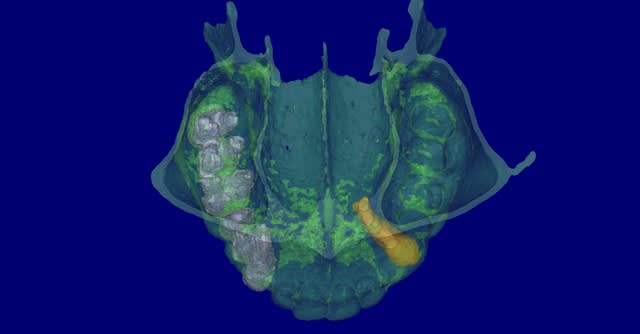

canine incluse

patiente de 80ans, canine incluse depuis donc pas mal de temps. ATCD de prothese amovible depuis 15ans. Je crains que sa canine soir hyper ankylosé et je me propose donc d'implanter au travers.

Canine axiale wvblwm - Eugenol